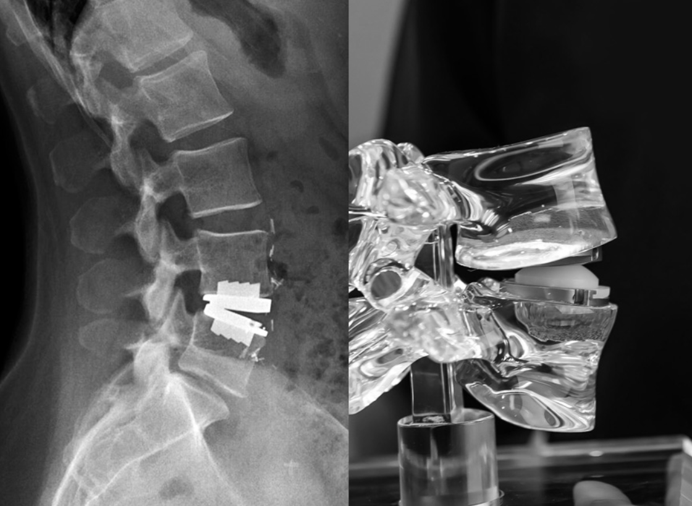

Dr. Khanna is also the recipient of the prestigious AO Spine International Fellowship from the globally renowned Schön Klinik, Munich, Germany, where he received training in advanced Endoscopic and Minimally Invasive Spine Surgery (MIS Spine Surgery).

Our team treats patients who need repair of spinal deformities due to scoliosis, kyphosis, spondylolisthesis, infection, tumors, and trauma — following international standards of care.